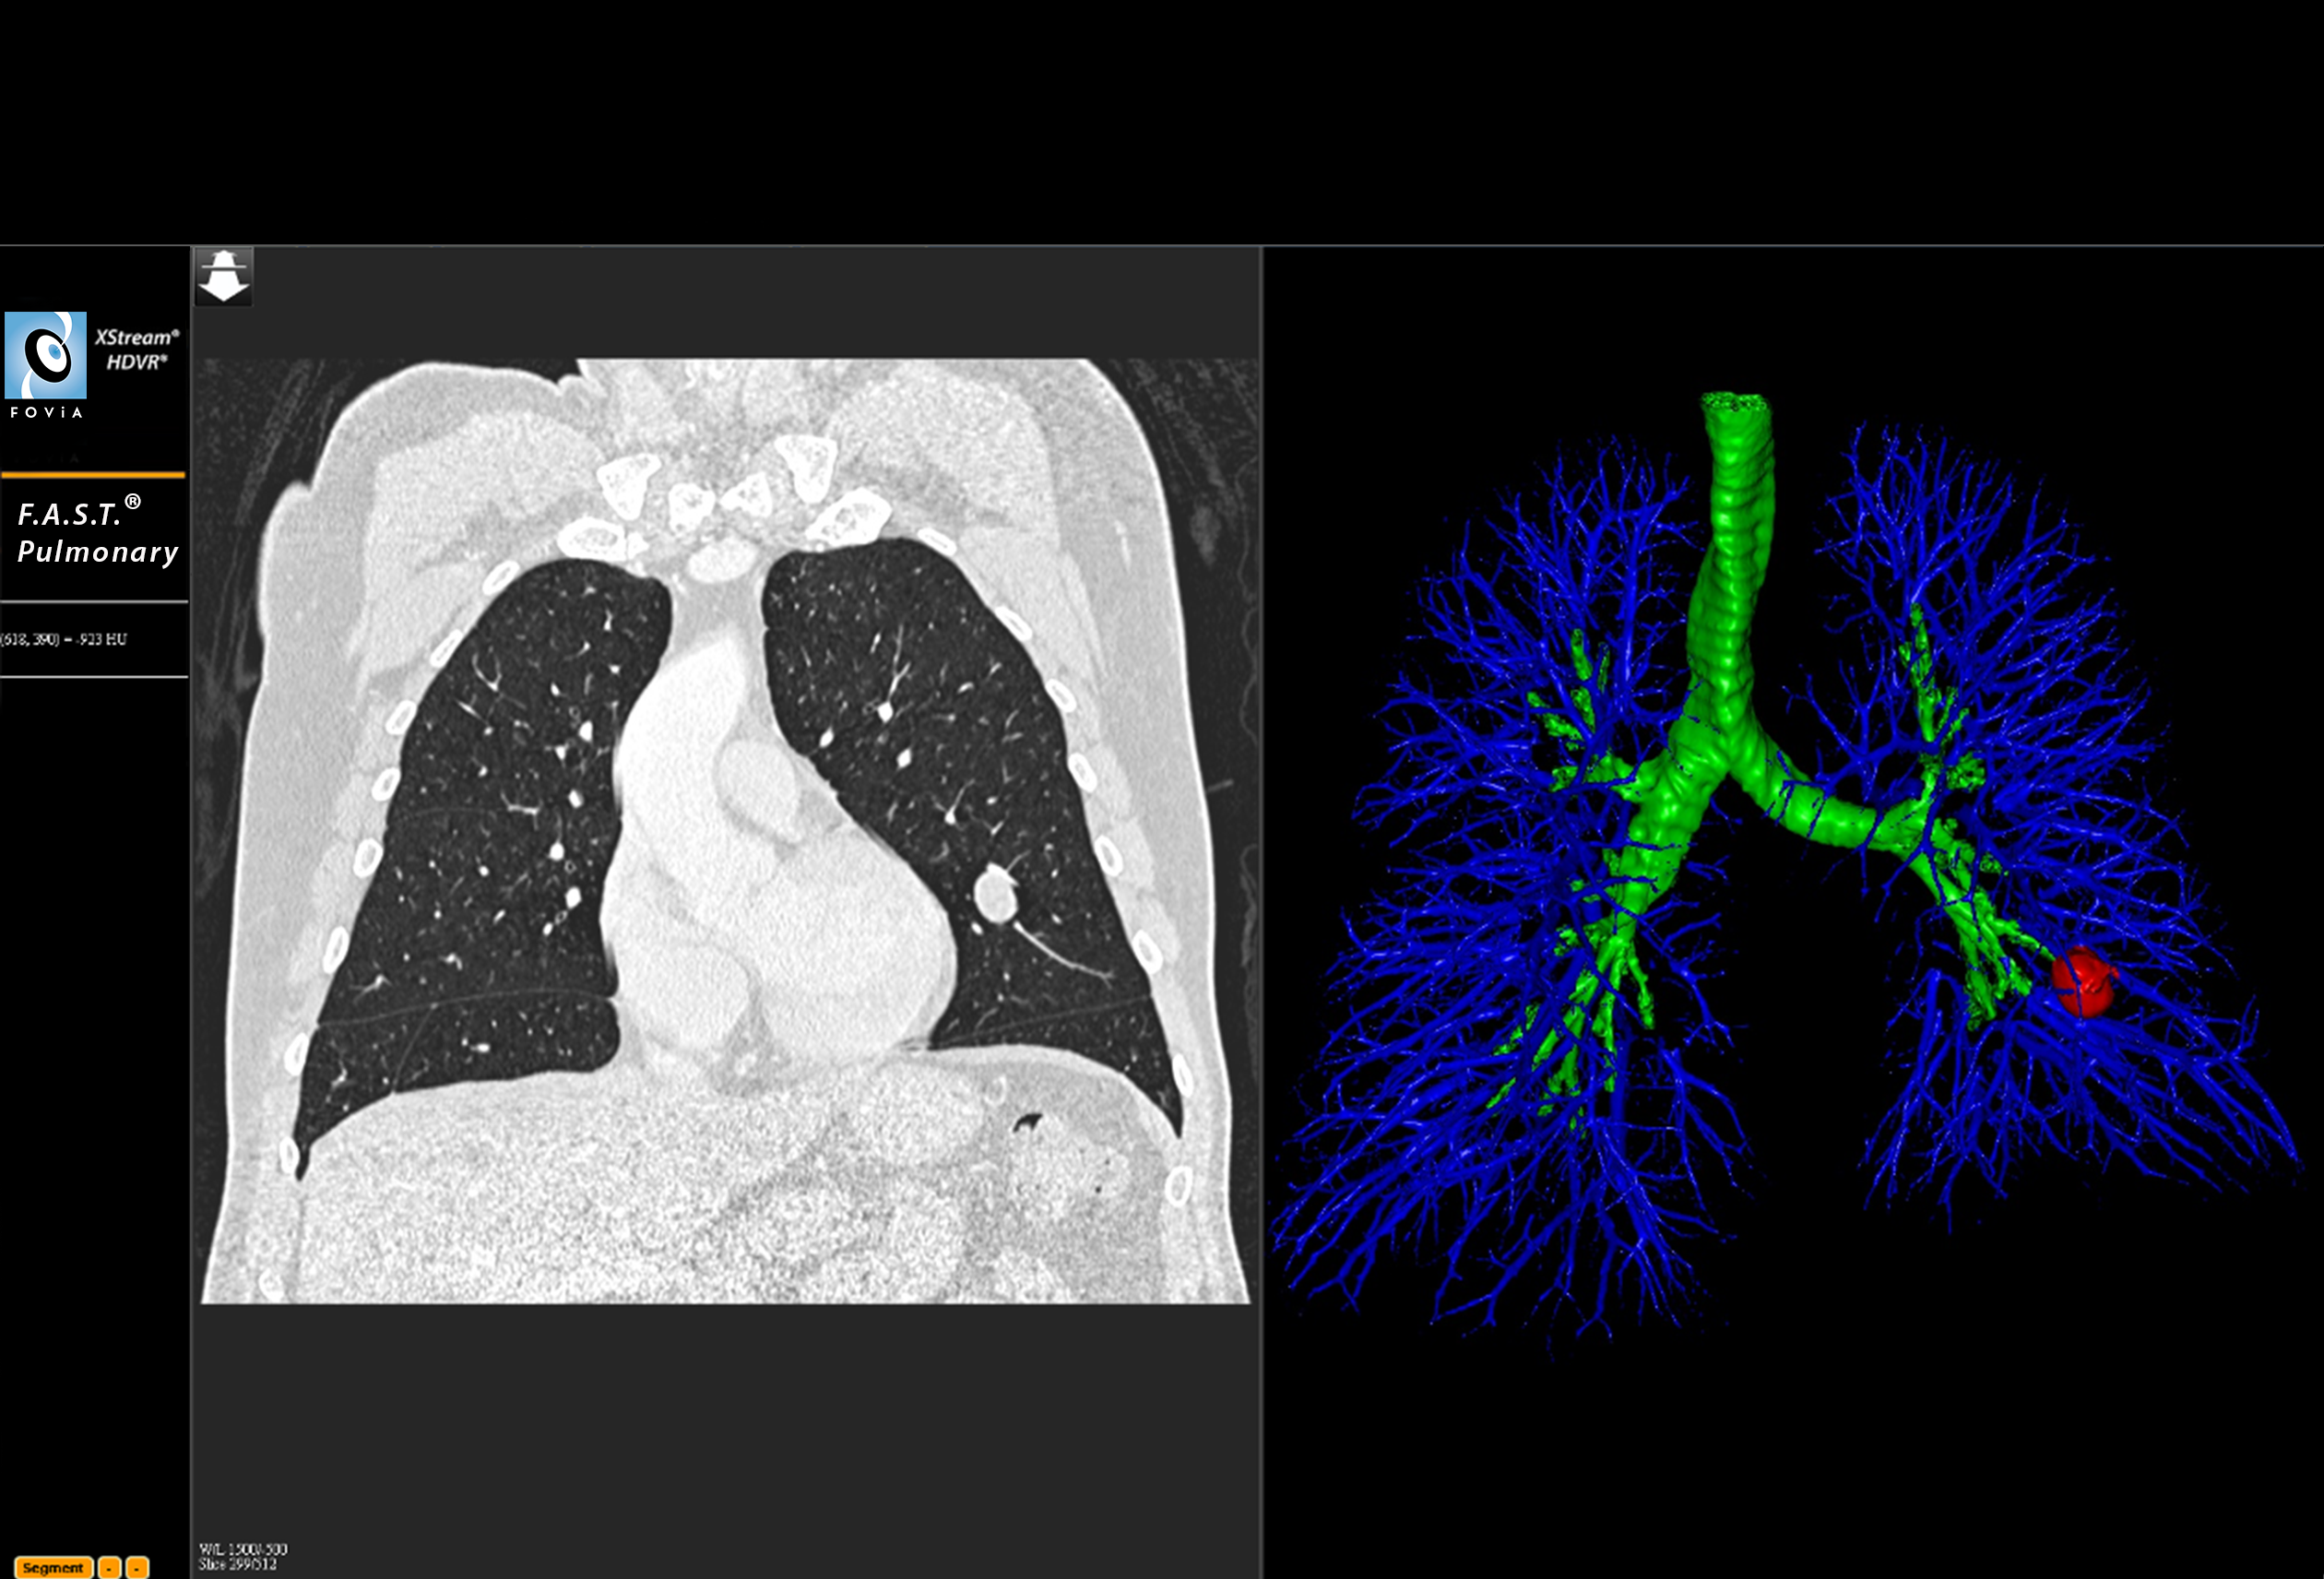

F.A.S.T. Pulmonary Workflow

F.A.S.T. Pulmonary Workflow